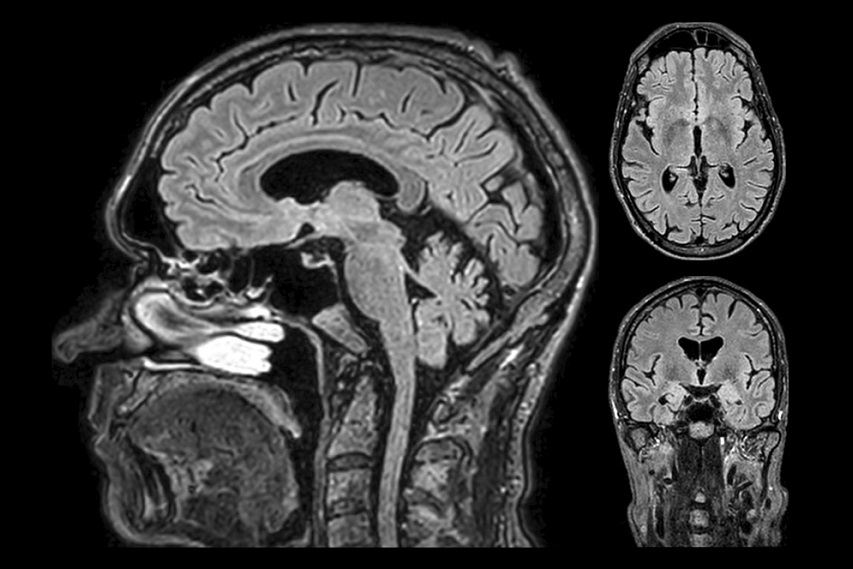

Com quase mil metros quadrados de área, o Hospital INC (Instituto de Neurologia de Curitiba) anuncia que vai operar o maior e mais moderno centro de diagnósticos e procedimentos de imagens da capital paranaense, o INC Imagem. O serviço funcionará no novo centro médico do Park Shopping Barigui, localizado no bairro Ecoville, e contará com equipamentos de última geração, como a primeira máquina de ressonância magnética sem hélio (wide bore) da cidade, que gera imagens de alta resolução de órgão e tecidos, com mais velocidade e conforto para o paciente.

“Com a ressonância magnética sem hélio, a instalação fica facilitada em locais de difícil acesso. Isso permite que mais pacientes se beneficiem de uma tecnologia que desempenha um papel essencial no diagnóstico das doenças mais prevalentes no mundo”, explica Felipe Basso, Zone Leader da Philips América Latina.